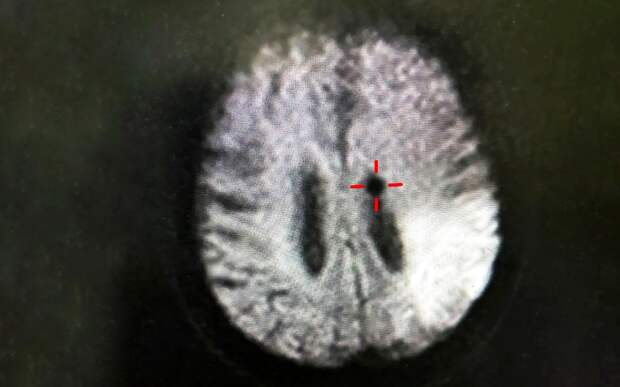

Врачи скорой помощи сразу поняли, что дело в инсульте. Рязанца экстренно доставили в больницу, где ему провели тромболитическую терапию - восстановили кровоток.